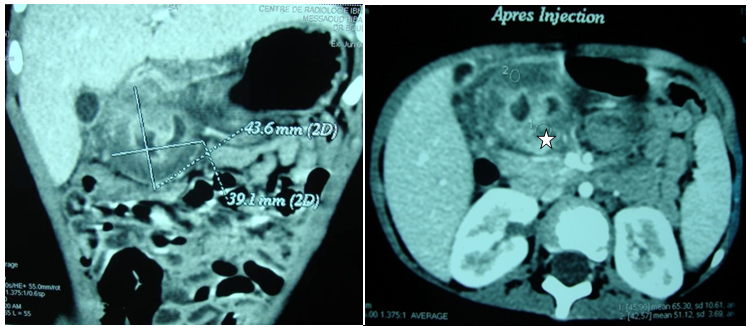

A two year old girl was presented in emergency for paroxystic abdominal pain without vomiting or other signs. The physical exam showed an epigastrium mass of 3cm which is round, tense, smooth and non tender beneath the umbilicus. Biologic exams were normal. Abdominal ultrasound with computer tomography revealed a cystic epigastric mass of 4.3cm with a wall that took contrast (Figure 3). Around this mass there was an ultrasound aspect of volvulus (Figure 4). A barium-meal examination demonstrated delayed gastric emptying through a narrowed pyloric antrum, which was distorted by a non communicating mass (Figure 5). At laparotomy, a cystic mass measuring approximately 4 × 3cm was identified anterior and lateral to the pyloric channel, sharing a common wall. The mass compressed the pyloric channel, resulting in partial gastric outlet obstruction. The duplication cyst did not communicate with the pyloric channel. Most of the cyst was excised, and the mucosa of the remnant cyst wall was cauterized. Histologic examination revealed gastric mucosa with a smooth muscle coat, which was consistent with a pyloric duplication cyst. No aberrant tissue was seen. The postoperative course was uneventful. The patient was asymptomatic 4years later.

Figure 3 Computer tomography: Cystic epigastric mass with a fine wall ( ☆ ) that took contrast.